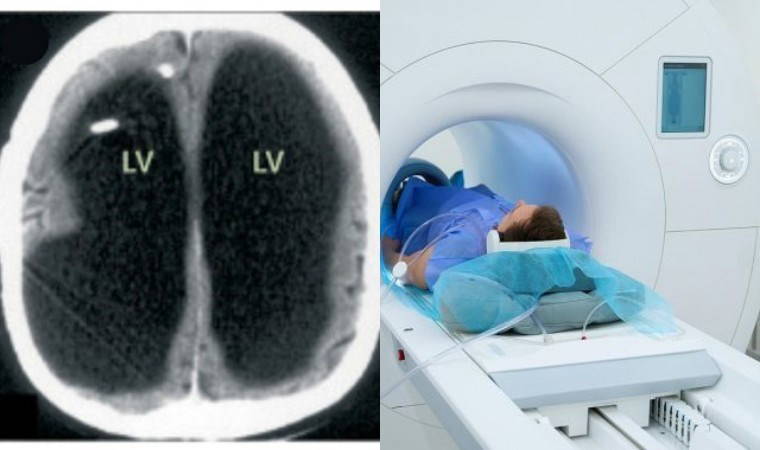

Hastaya yapılan CT ve MRI taramalarında doktorlar inanılmaz bir manzarayla karşılaştı: Beyninin büyük bir bölümü yerinde yoktu, bunun yerine devasa bir sıvı cebi bulunuyordu. Tıp dünyasında oldukça nadir görülen bir durum olan ciddi hidrosefali teşhisi konuldu.

Tıp dergisi The Lancet’te paylaşılan beyin taramalarında, beynin ana bölgesinin büyük ölçüde siyah göründüğü, bunun da sıvı birikimine işaret ettiği belirtildi. Bu durum, beyninin sıkışarak ince bir tabaka halinde kafatasının kenarına itilmesine neden olmuştu.